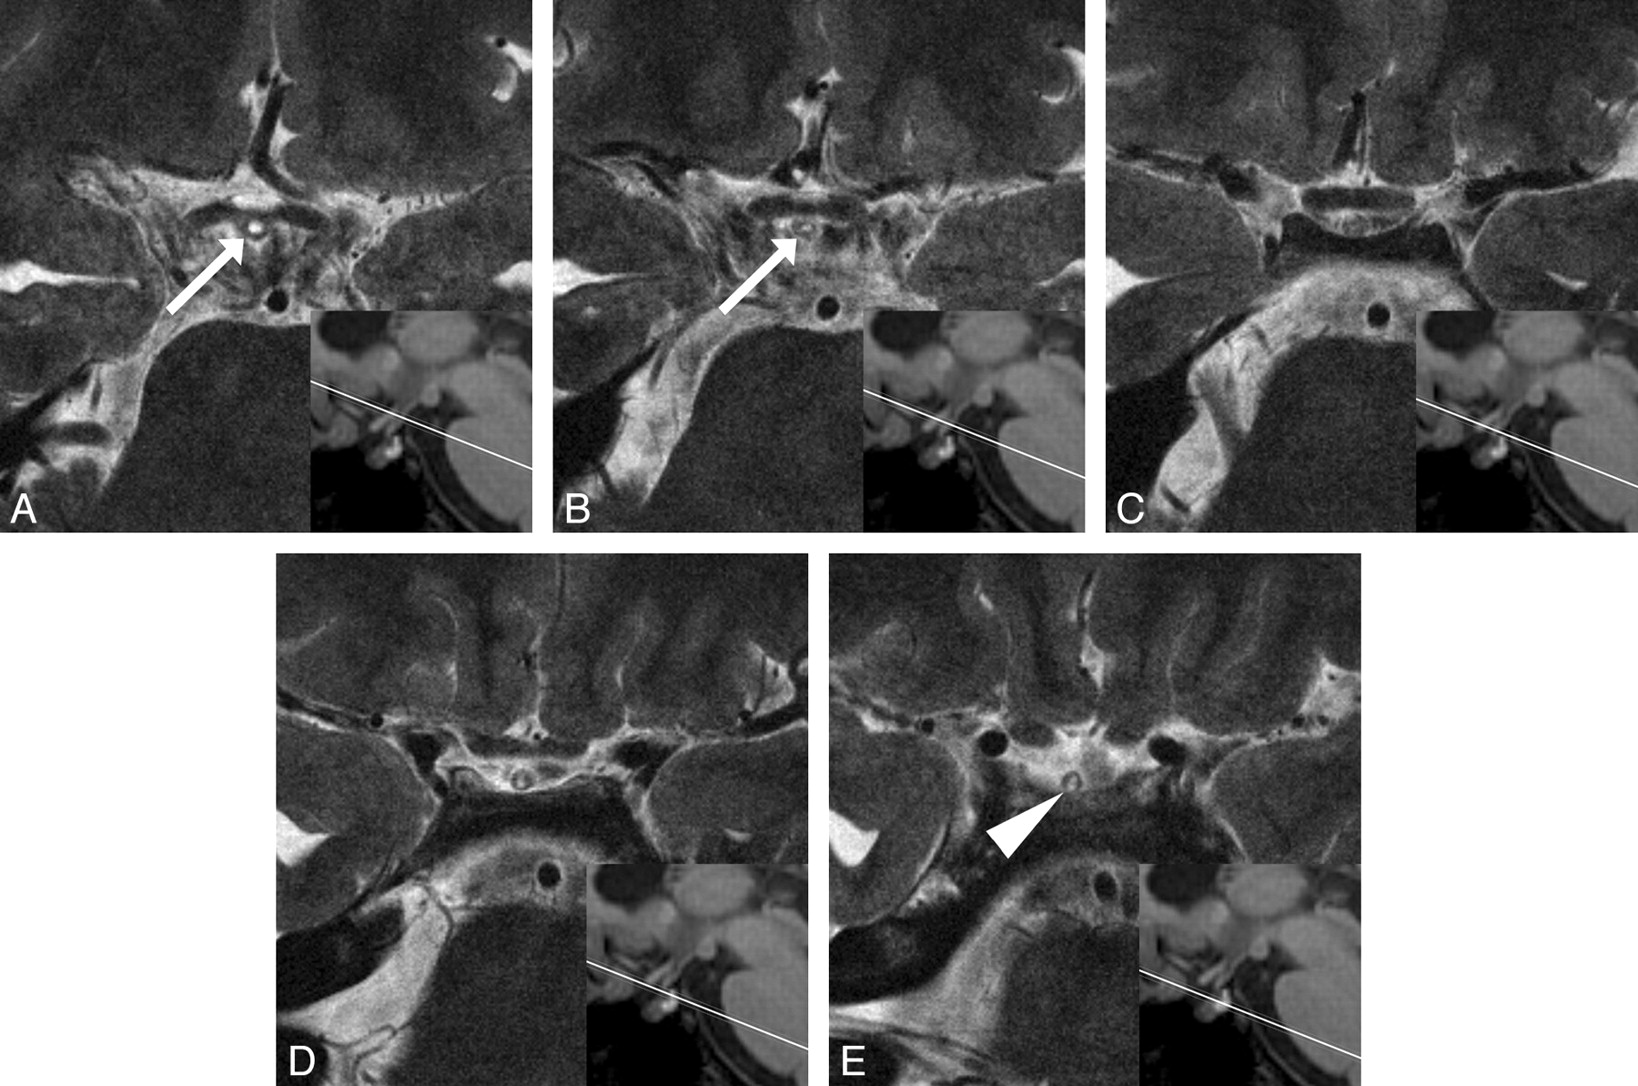

T2-weighted oblique-axial images of the pituitary stalk of a 34-year-old healthy woman. Consecutive images with 2-mm intervals are presented from superior (A) to inferior (E), along with a reference line of each imaged level on the midsagittal MPRAGE image. The infundibular recess (arrows) ends at the midstalk level. The parenchyma of the pituitary stalk at its insertion on the pituitary gland shows central hyperintensity with a peripheral rim of isointensity (arrowhead) compared with the cerebral white matter.